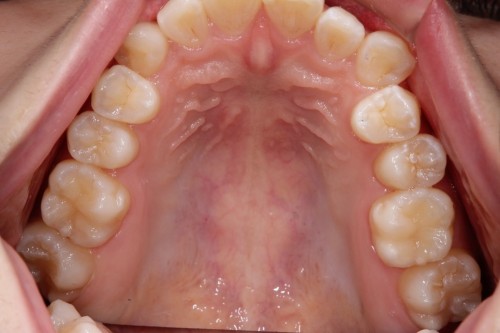

左右のダイレクトボンディング

費用5万円×4本

リスクとして欠ける可能性がある(修復可能)。